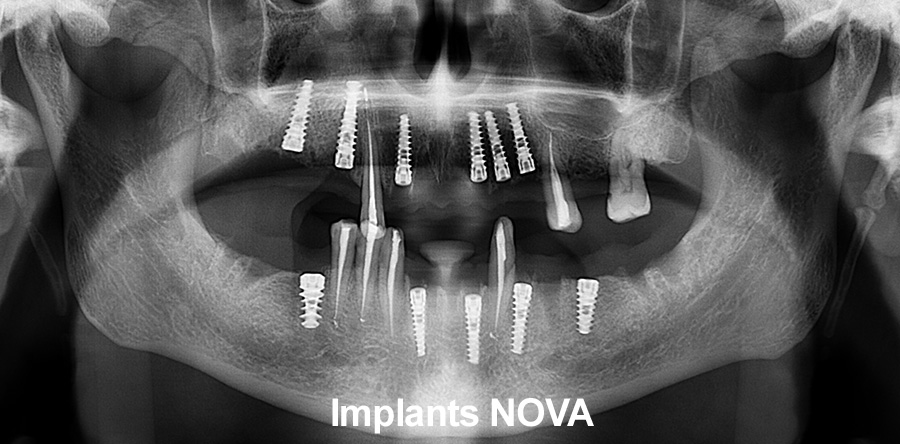

Рентген имплантов Alpha Bio: диагностика и качество